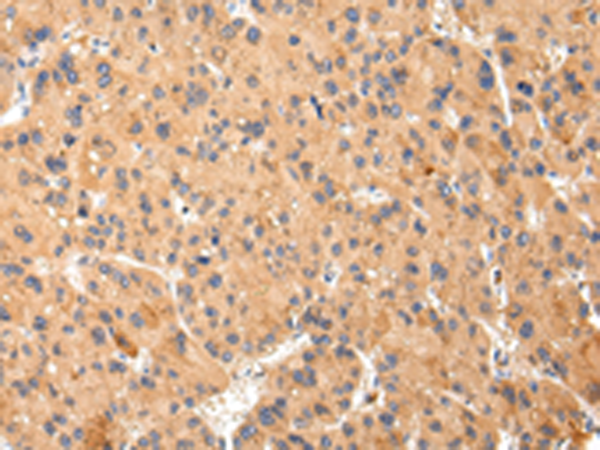

分类: 科研抗体货号: P12470别名: MRP; ABCC; GS-X; MRP1; ABC29应用: WB,IHC反应种属: Human